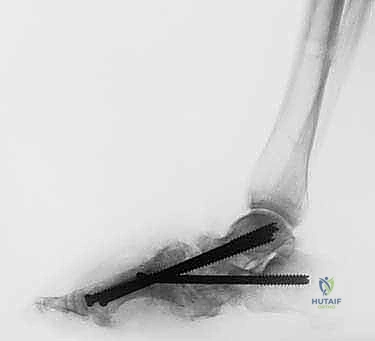

تثبيت مفصل الكاحل الأمامي: حل فعال لخشونة الكاحل المزمنة مع الأستاذ الدكتور محمد هطيف

تعرف على تثبيت مفصل الكاحل الأمامي لعلاج خشونة الكاحل المتقدمة. اكتشف الأعراض، التشخيص، والخطوات الجراحية مع الأستاذ الدكتور محمد هطيف في ص…